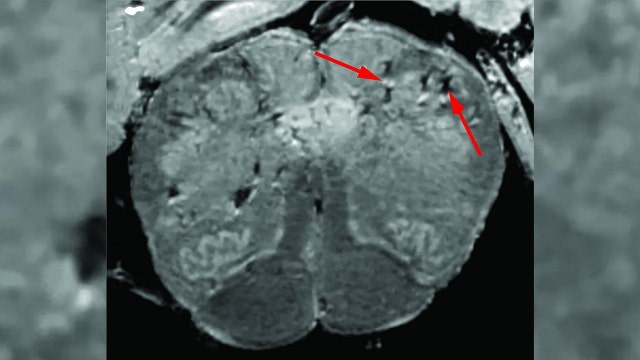

Amid increasing evidence of lasting neurological effects from COVID-19, the National Institutes of Health said it has launched an online database in order to track these symptoms in hopes of better understanding how the coronavirus impacts the brain and nervous system.